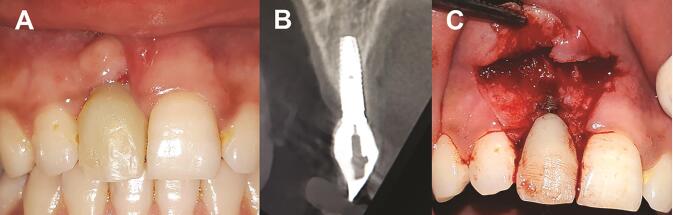

Peri-implantitis Clinical Manifestation

Peri-implantitis: ( A ) clinical photograph, ( B ) radiograph showing bone loss around an implant, and ( C ) clinical photograph showing buccal bone loss.